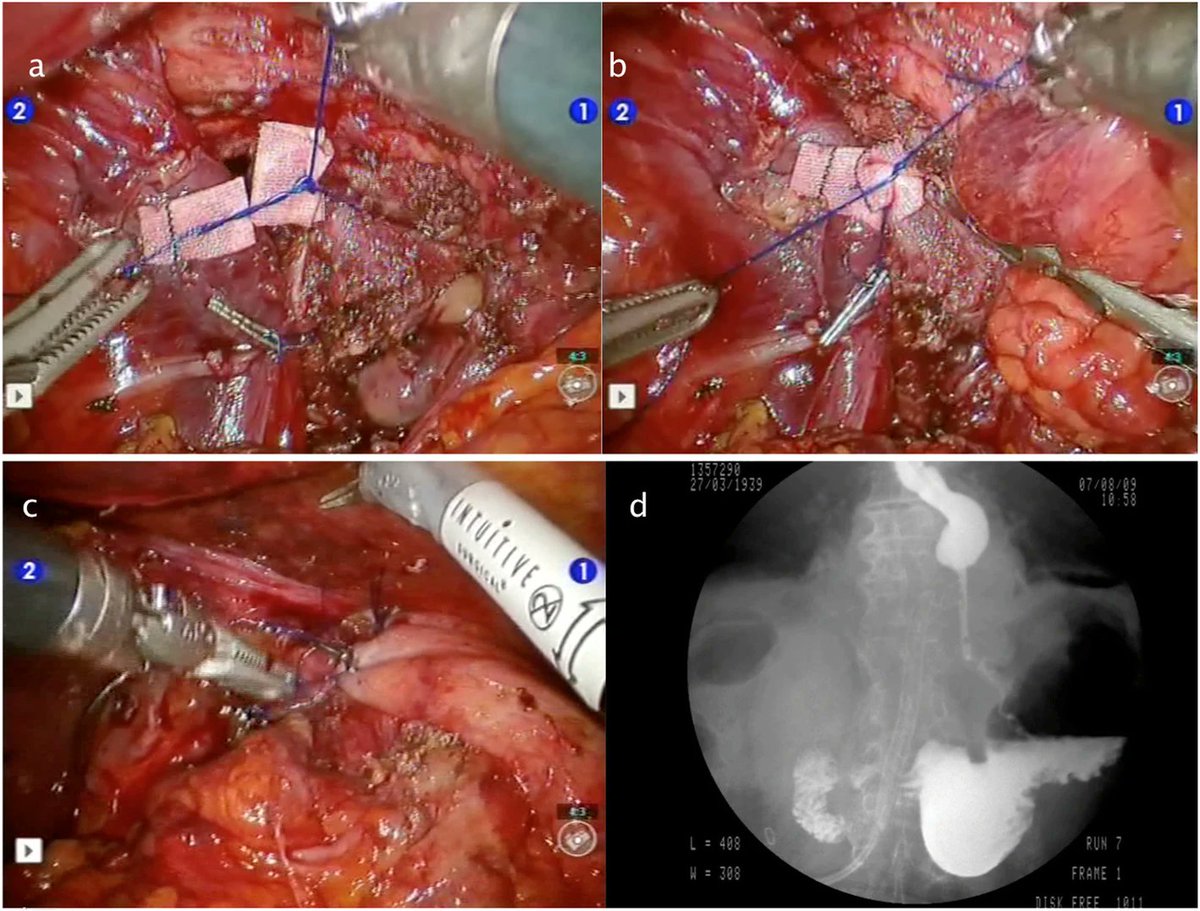

Pledgeted 3-0 Prolene sutures are often used for cardiac repair for trauma.

Here is a repair I did for blunt injury (that is to say, my R3 resident placed the actual sutures).

This time, I remembered the reference: